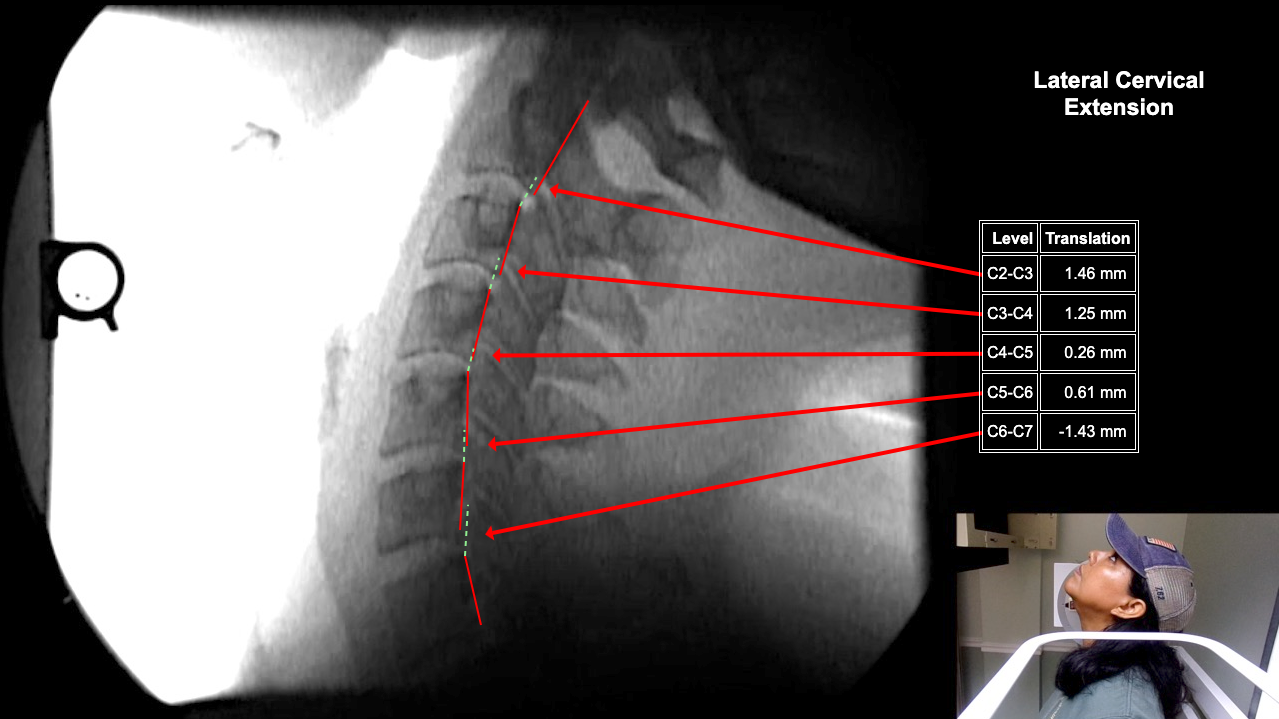

Home > Tamara Tripp 7-3-25